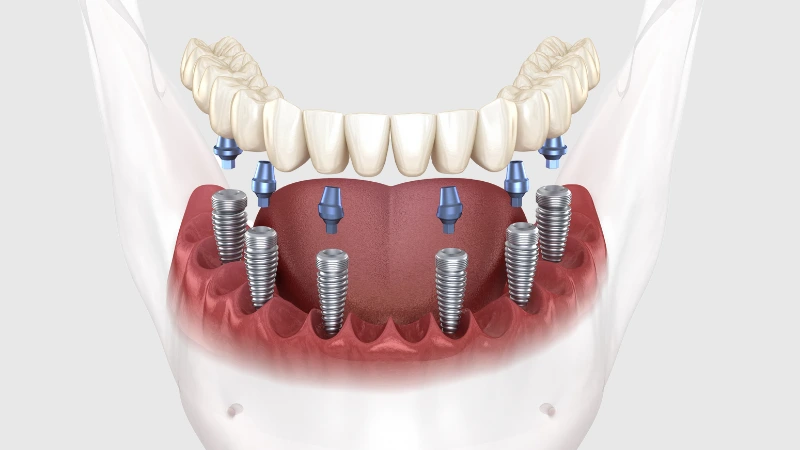

All on 6

All on 6 si riferisce all’impianto chirurgico di sei impianti nella mascella superiore e inferiore. I due impianti dentali aggiuntivi di all-on-4 potrebbero essere necessari per garantire stabilità e forza in bocca, aumentando le probabilità di successo della tua nuova protesi permanente. Per quei pazienti in cui la carie dell’osso mascellare rappresenta un problema, l’impianto dentale all on 6 offre ulteriore rafforzamento e stimolazione all’osso mascellare. I nostri dentisti esperti ti consiglieranno ciò che è meglio per le tue esigenze.

All on 8

Tutti gli 8 impianti dentali vengono utilizzati in pazienti che richiedono una maggiore sicurezza dei loro impianti ad arcata completa. Ciò potrebbe essere dovuto alla scarsa densità della mascella, alla forma irregolare della bocca o a qualsiasi altro problema riscontrato dal dentista.